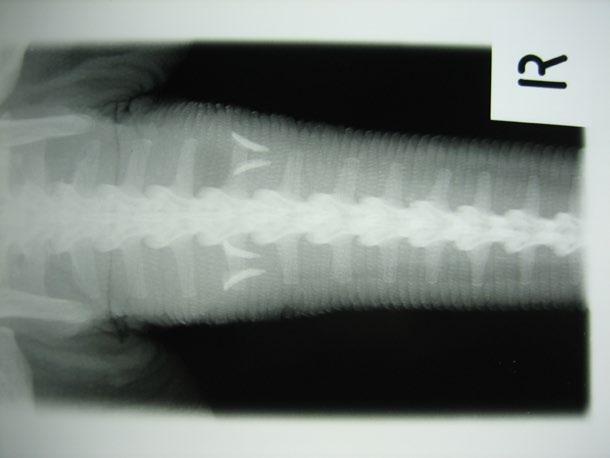

Cha Cha is a 9-month-old male neutered Domestic Shorthair cat. He was initially seen by another clinic for straining to defecate and blood in the stool. He was otherwise very bright, active, eating well and in good body condition.

An ultrasound at the other clinic identified marked thickening of the descending colon.

The owners were advised that this was most likely to be neoplastic and were advised to undertake a subtotal colectomy.

The owners came to us for a second opinion. Our ultrasound confirmed the findings of the previous clinic. There was a marked focal thickening of the descending colon:

Figure 2. Ultrasound image of the caudal abdomen showing marked thickening (10.9 mm) of the descending colon

Although neoplasia was indeed considered in the differential diagnosis, a recent publication (Müller et al JFMS 2023—Abdominal ultrasonographic findings of cats with feline infectious peritonitis—an update) had also indicated that this was amongst the increasingly varied recognised presentations for FIP. Indeed, historically it was referred to as ‘focal FIP’.

We considered the lesion to be accessible to colonoscopic biopsy, and so this was conducted, in an attempt to obtain a definitive diagnosis.

The lesion was readily accessible to endoscopic biopsy but unfortunately the results were inconclusive. Lymphoma was considered unlikely, and there was no indication of any other neoplasia.

Several years ago, we would have recommended exploratory laparotomy at this point.

Without a definitive diagnosis, and with FIP still considered a fatal disease, excision biopsy would have been the most appropriate clinical recommendation.

However, over the last few years, the treatment of FIP has been revolutionised by highly effective antiviral medications with excellent safety profiles. After a difficult period in which these medications were only available from the black market and of dubious quality, these drugs have now become safe and readily available in most jurisdictions.

We discussed with Cha Cha’s owner the option of a therapeutic trial with the antiviral nucleoside analogue GS-441524, now known affectionately all over Hong Kong simply as ‘四四一’ (Cantonese for ‘four four one’). Keen to avoid invasive surgery at all costs, the owners readily consented.

The results were nothing less than stunning.

After weeks of relentlessly worsening dyschezia, Cha Cha’s symptoms disappeared within 2 days.

A repeat ultrasound after 10 days of treatment indicated early evidence of a reduction of the colonic lesion.

The treatment was extended.

Treatment protocols for FIP have been rapidly refined in a short space of time due to the sudden widespread availability of effective antivirals, such as GS-441524.

After an initial recommendation for 84 days of treatment, a recent study showed 42 days to be equally effective (Zuzzi-Krebitz et al Viruses 2024—Short Treatment of 42 Days with Oral GS-441524). Worthy of note is the fact that cases in this study were predominantly ‘wet’, and there is some evidence to suggest that longer courses may still be required for successful and definitive treatment of other forms (e.g. ‘dry’, focal, CNS, and/or ocular disease).

We planned to provide 42 days of treatment and serially assess the lesion by ultrasound to determine the effect of the treatment.

There were no side effects from the medications at any time.

Here are the sequential images:

At the time of writing, 1 month after completion of a 42 day course of medication, Cha Cha is asymptomatic, with no clinical, clinical pathological, or sonographically detectable signs of disease. This response is very difficult to attribute to anything other than highly effective treatment of focal, colonic ‘dry’ FIP with GS-441524.